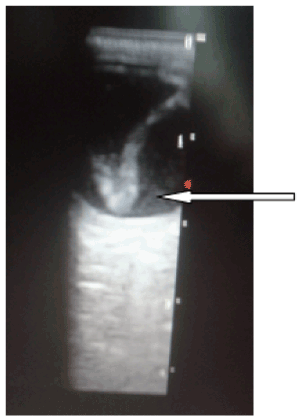

Figure 1. Coned section of an ocular echogram showing the globulous crystalline lens [white arrow] that has migrated to the posterior vitreous (a dependent position) and abutting the papilla and adjacent retina of the right eye of a patient (Complete dislocation of the lens of the right eye)